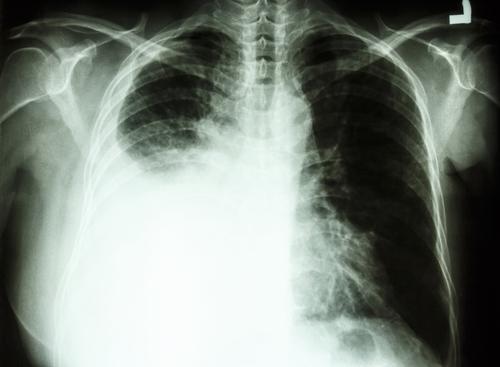

Le scanner thoracique est en outre inadapté : il génère trop de résultats dits « faux positifs », c’est-à-dire qui suggèrent la présence d’une tumeur qui n’existe pas. Sans compter les risques liés à l’irradiation d’une partie du thorax de manière répétée, qui dépassent de loin les bénéfices d’une telle pratique.